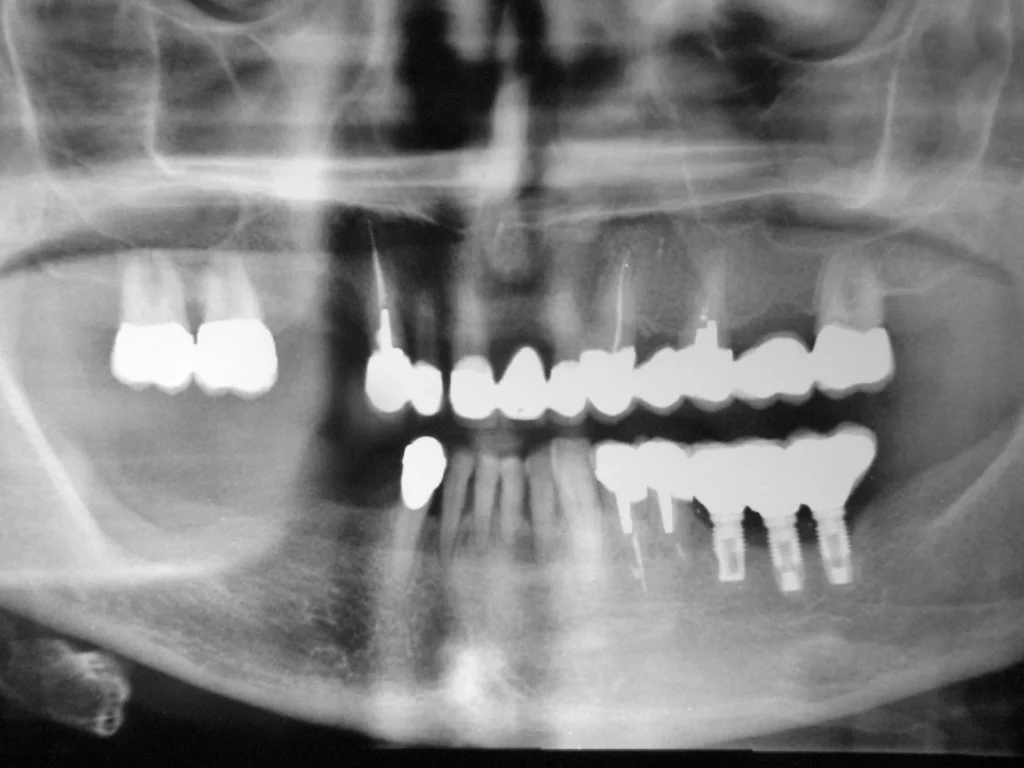

Le radiografie endorali e panoramiche post-operatorie permettono di visualizzare la quantità di osso neoformato, confrontandolo con immagini pre-operatorie.

Le CBCT (Tomografie computerizzate a fascio conico) sono spesso impiegate per un’analisi tridimensionale più precisa del volume osseo rigenerato.